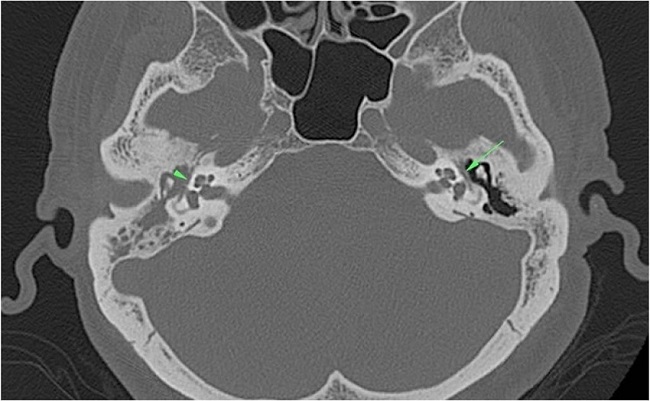

Dehiscence of the facial canal was observed in 62 (54.8%) of the 113 patients. A total of 52 out of the 62 patients had dehiscence in the tympanic segment of the facial canal (Fig. 3), eight in the mastoid segment, one in the geniculate ganglion level, and one in the genu of the tympanic segment.

Selesnick and Lynn-Macrae evaluated the incidence of facial canal dehiscence in a study of 67 cholesteatoma cases.7 They found facial canal dehiscences in 30% of the initial surgical procedures and in 35% of the revision procedures. They reported that the tympanic segment was the most common region (81%) of facial canal dehiscence occurrence.7 Kim et al. reviewed 152 patients for intraoperative findings of facial canal dehiscence and observed facial canal dehiscence in 13 (8.6%) of 152 patients.2 The most commonly involved region was the tympanic segment, which accounted for 84.6% of the incidence of canal dehiscence. Facial canal dehiscence was noted on the lateral aspect of the facial canal in the oval window area at an incidence of 69.2%.2 In our study, 113 patients who had pathologically proven middle ear cholesteatoma were included, and 62 of 113 patients had surgically confirmed facial canal dehiscence while 51 did not. The incidence of facial nerve canal dehiscence in patients with cholesteatoma was 54.8%. Dehiscence was found in 52 of 62 cases in the tympanic segment of the facial canal, eight were found in the mastoid segment, one was found in the geniculate ganglion, and the other was found in the second genu.